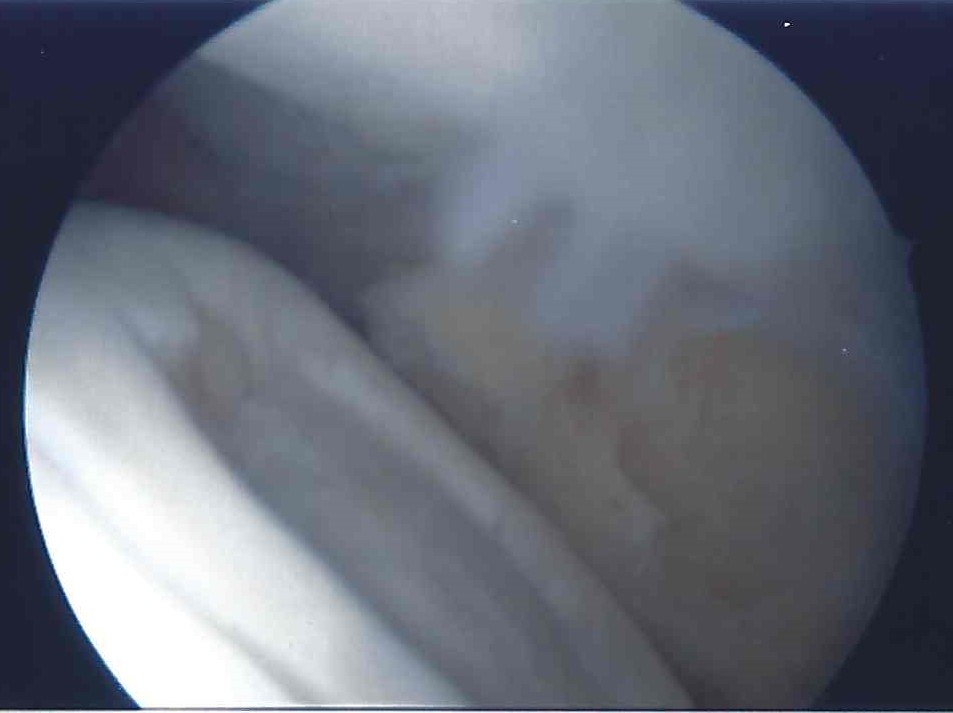

ASKP KNorpeldefekt nach Präparation